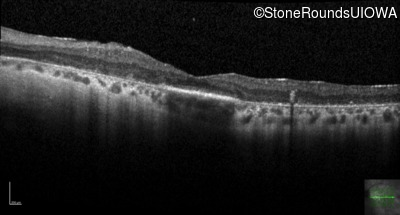

Optical Coherence Tomography - Right - 20/70

Exemplar / OCT Stack

Optical Coherence Tomography - Left - 20/70

OCT Stack